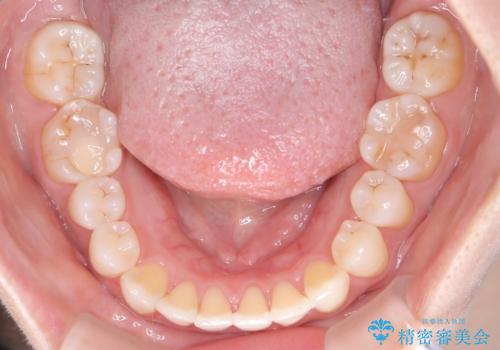

【開咬】笑った時の見た目を改善したい。

- 重度の開咬でしたがインビザラインで適切に治療計画を立て、きれいに仕上がりました。

インビザラインは開咬の治療に向いています。